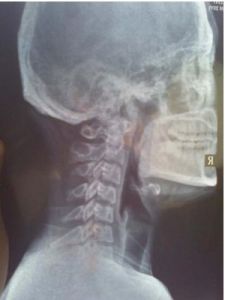

頸椎反弓影像圖人類屬於高級脊椎動物,頸椎“C”形向前的生理弧線保證了頸椎活動的高度靈活性,但人們常常發生違背頸椎生理曲線的姿態和活動。

頸椎反弓是構成頸椎病最常見的病理基礎,而不適當用枕是導致頸椎反弓的重要原因。

頸椎反弓治療對比圖牽引治療頸椎間盤突出症可增大椎間隙和椎間孔, 解除頸部軟組織痙攣, 從而減少對椎間盤的壓力, 力圖使突出的髓核回納, 使神經根和椎動脈受到的刺激和壓迫得以緩解, 突出物和周圍組織的粘連也相應得以緩解。推拿治療可使頸部疼痛肌肉放鬆, 促進局部血液循環, 有助於稀釋致痛物質, 加速代謝產物排泄, 促使局部水腫吸收。另一方面利用鏇轉“復位”法可使突出的椎間盤移位變形, 亦解除對神經根的壓迫, 增強頸椎關節穩定性, 使頸椎的內外環境平衡。